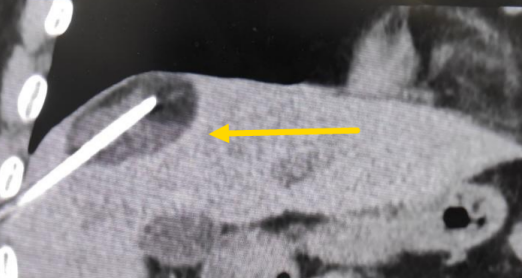

經(jīng)過(guò)多學(xué)科討論,陳寶瑩主任根據(jù)影像資料指出,患者轉(zhuǎn)移瘤位于腹膜后,內(nèi)側(cè)瀕臨人體最大的血管——主動(dòng)脈;前方同樣有血管緊貼腫瘤;外側(cè)是腎臟,后方是椎體和神經(jīng),夾縫中進(jìn)針難度大,治療時(shí)要避免周圍重要臟器、血管和神經(jīng)的損傷,因此可以選擇CT引導(dǎo)下精準(zhǔn)穿刺活檢同步冷凍消融治療,即獲得病理組織有利于下一步全身治療方案的調(diào)整,同時(shí)殺死腹膜后轉(zhuǎn)移瘤,周圍正常組織損傷的可能性也小。

術(shù)中陳寶瑩主任、李鐵柱教授、兀云飛醫(yī)生、魏東紅技師、汝平護(hù)士協(xié)調(diào)配合,夾縫進(jìn)針難度雖大,但在CT引導(dǎo)下逐步進(jìn)針,精準(zhǔn)到位,順利活檢取得組織,由于腫瘤較大,為了提高消融效率,平行置入兩根冷凍消融針,同時(shí)啟動(dòng)冷凍消融,術(shù)中清晰觀察到冰球完全覆蓋病變,患者沒有任何不舒服,治療中還可以和醫(yī)生聊天。